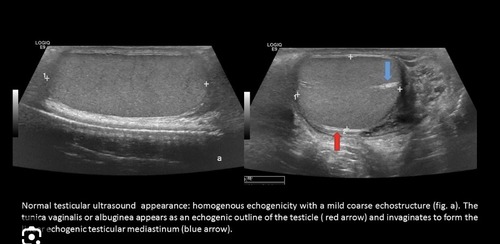

THIS IMAGE REPRESENTS WHICH OF THE FOLLOWING:

transverse view of the thyroid

transverse view of the testicles

dual image of the scrotum

a longitudinal view of the left testicle

Testicular parenchyma on ultrasound is:

homogeneous.

heterogeneous.

anechoic.

mixed solid appearance.

What is the echogenicity of the mediastinum testis?

Low-level echoes

Medium-level echoes

High echogenicity

It cannot be identified on ultrasound.